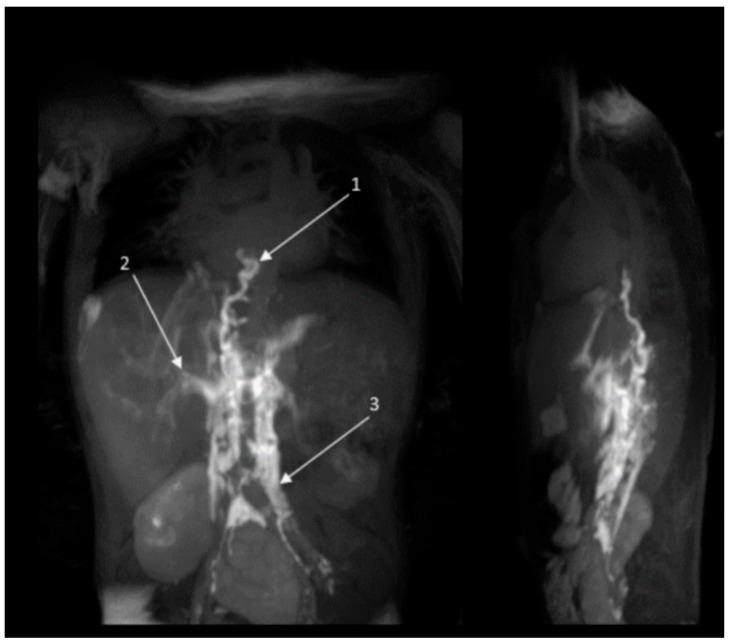

努南综合征及相关疾病患者复杂淋巴管异常的靶向治疗

Recent diagnostic advances reveal that lymphatic disease in Noonan syndrome (NS) and other NS-like RASopathies often stems from central conducting lymphatic anomalies (CCLAs). The RAS/MAPK-ERK pathway plays a central role in lymphangiogenesis. Targeting this pathway with MEK-inhibitor trametinib has emerged as a promising therapeutic strategy for managing CCLAs in patients with NS-like RASopathies. This case series assessed the clinical outcomes of trametinib therapy in eight patients with NS-like RASopathies and CCLA, each offering unique insights into the therapeutic efficacy of MEK inhibition. In infants, a lower dose of 0.01 mg/kg/day and earlier discontinuation of trametinib therapy effectively alleviated the symptoms of congenital chylothorax and rescued the lymphatic phenotype, compared to similar published cases. Moreover, four patients aged >11 y showed a slower response and did not achieve complete symptomatic recovery. In conclusion, it is advised to consider trametinib therapy for patients with severe, therapy-refractory CCLA in patients with NS-like RASopathies. However, individual responses to trametinib therapy may vary, with some patients demonstrating more favorable outcomes than others. Further investigation into potential enhancers and suppressors of the lymphatic phenotype is necessary for more accurate treatment predictions. While these factors are likely genetic, we cannot rule out other intrinsic or physiological factors.

近期的诊断进展表明,努南综合征(NS)及其他类NS型RAS病中的淋巴疾病通常源于中央传导性淋巴管异常(CCLA)。RAS/MAPK-ERK信号通路在淋巴管生成中起核心作用。使用MEK抑制剂曲美替尼靶向该信号通路已成为治疗类NS型RAS病患者CCLA的一种有前景的治疗策略。本病例系列评估了曲美替尼治疗8例类NS型RAS病和CCLA患者的临床结局,每例患者都为MEK抑制的治疗效果提供了独特见解。与已发表的类似病例相比,婴儿使用较低剂量0.01 mg/kg/天并更早停用曲美替尼治疗可有效缓解先天性乳糜胸症状并挽救淋巴管表型。此外,4例年龄大于11岁的患者反应较慢,未实现症状完全缓解。总之,对于类NS型RAS病中患有严重、难治性CCLA的患者,建议考虑使用曲美替尼治疗。然而,患者对曲美替尼治疗的个体反应可能不同,部分患者的预后比其他患者更好。为了进行更准确的治疗预测,有必要进一步研究淋巴管表型的潜在增强剂和抑制剂。虽然这些因素可能是遗传性的,但我们不能排除其他内在或生理因素。